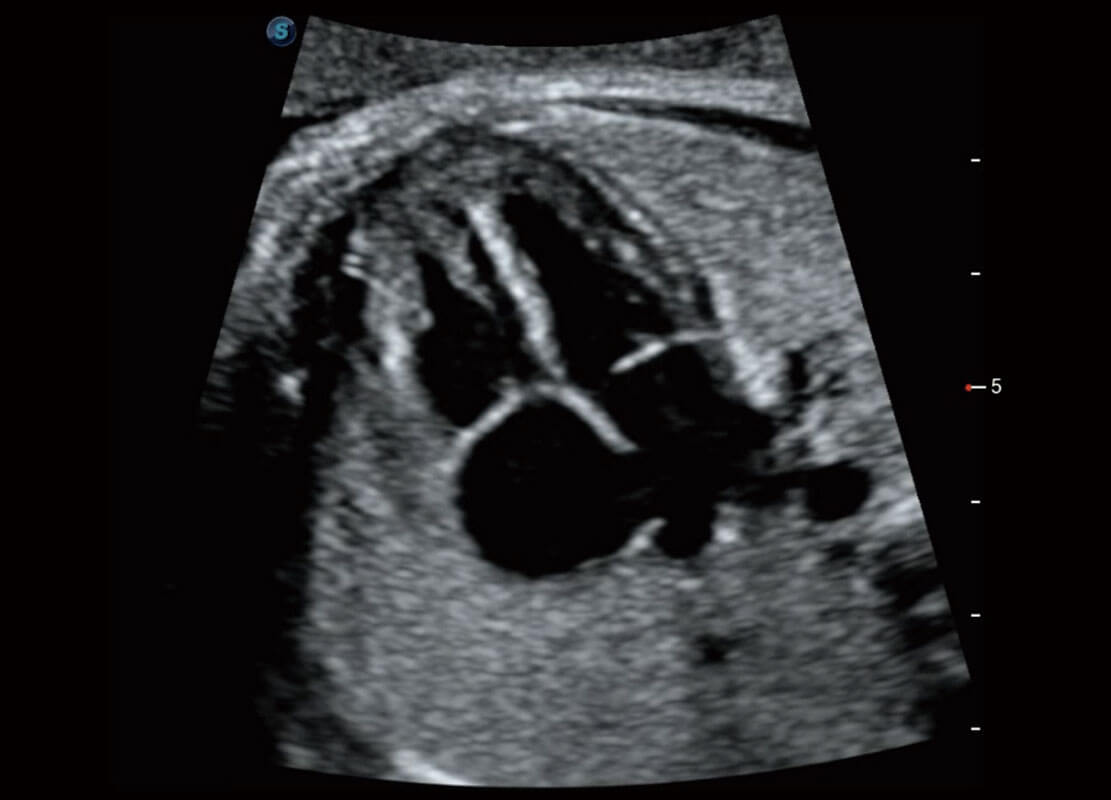

• 腔内三维-宫内节育器

• 腔内三维-光影成像